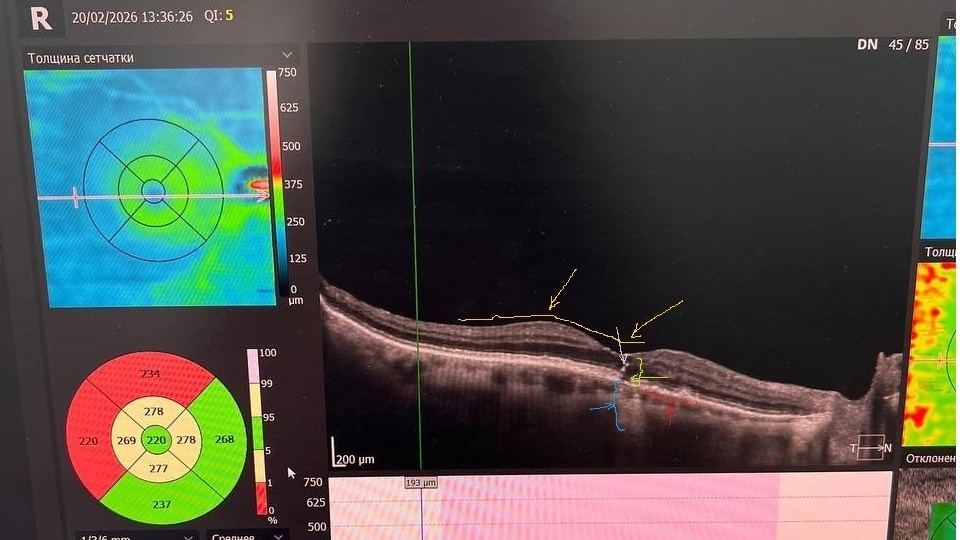

Клинический случай полного макулярного разрыва в сочетании с географической атрофией сетчатки

Статью подготовил врач-офтальмолог Владимирова Ю.В. В клинику «Олимп Здоровья» обратилась пациентка М., 1938 г.р., с жалобами на снижение зрения вдаль и вблизи правого и левого глаз, наличие «пятна» перед левым глазом и искажение линий перед правым глазом. Пациентка оперирована по поводу катаракты дважды в 2018 г., однако желаемая острота зрения достигнута не была. Носит очки для чтения, но коррекция не удовлетворяет, отмечает наличие «черных пятен» перед глазами. Наследственный анамнез не отягощен. Наблюдается у кардиолога и терапевта по поводу гипертонической болезни и ОНМК. OD 0,4 н/к; вблизи 0,3 sph +2.50 = 1,0

OS 0,1 н/к (эксцентрично); вблизи 0,3 sph +2.50 («через пятно в центре») = 1,0 OD 11 мм рт. ст.

OS 10 мм рт. ст. OU: макулярный рефлекс.

OD - сглажен, единичные участки атрофии ПЭС, твердые друзы.

OS - рефлекс отсутствует, «географическая» атрофия, неравномерная пигментация, множественные твердые друзы, в фовеоле разрыв со слабопигментированными краями. OU - небольшое разреж